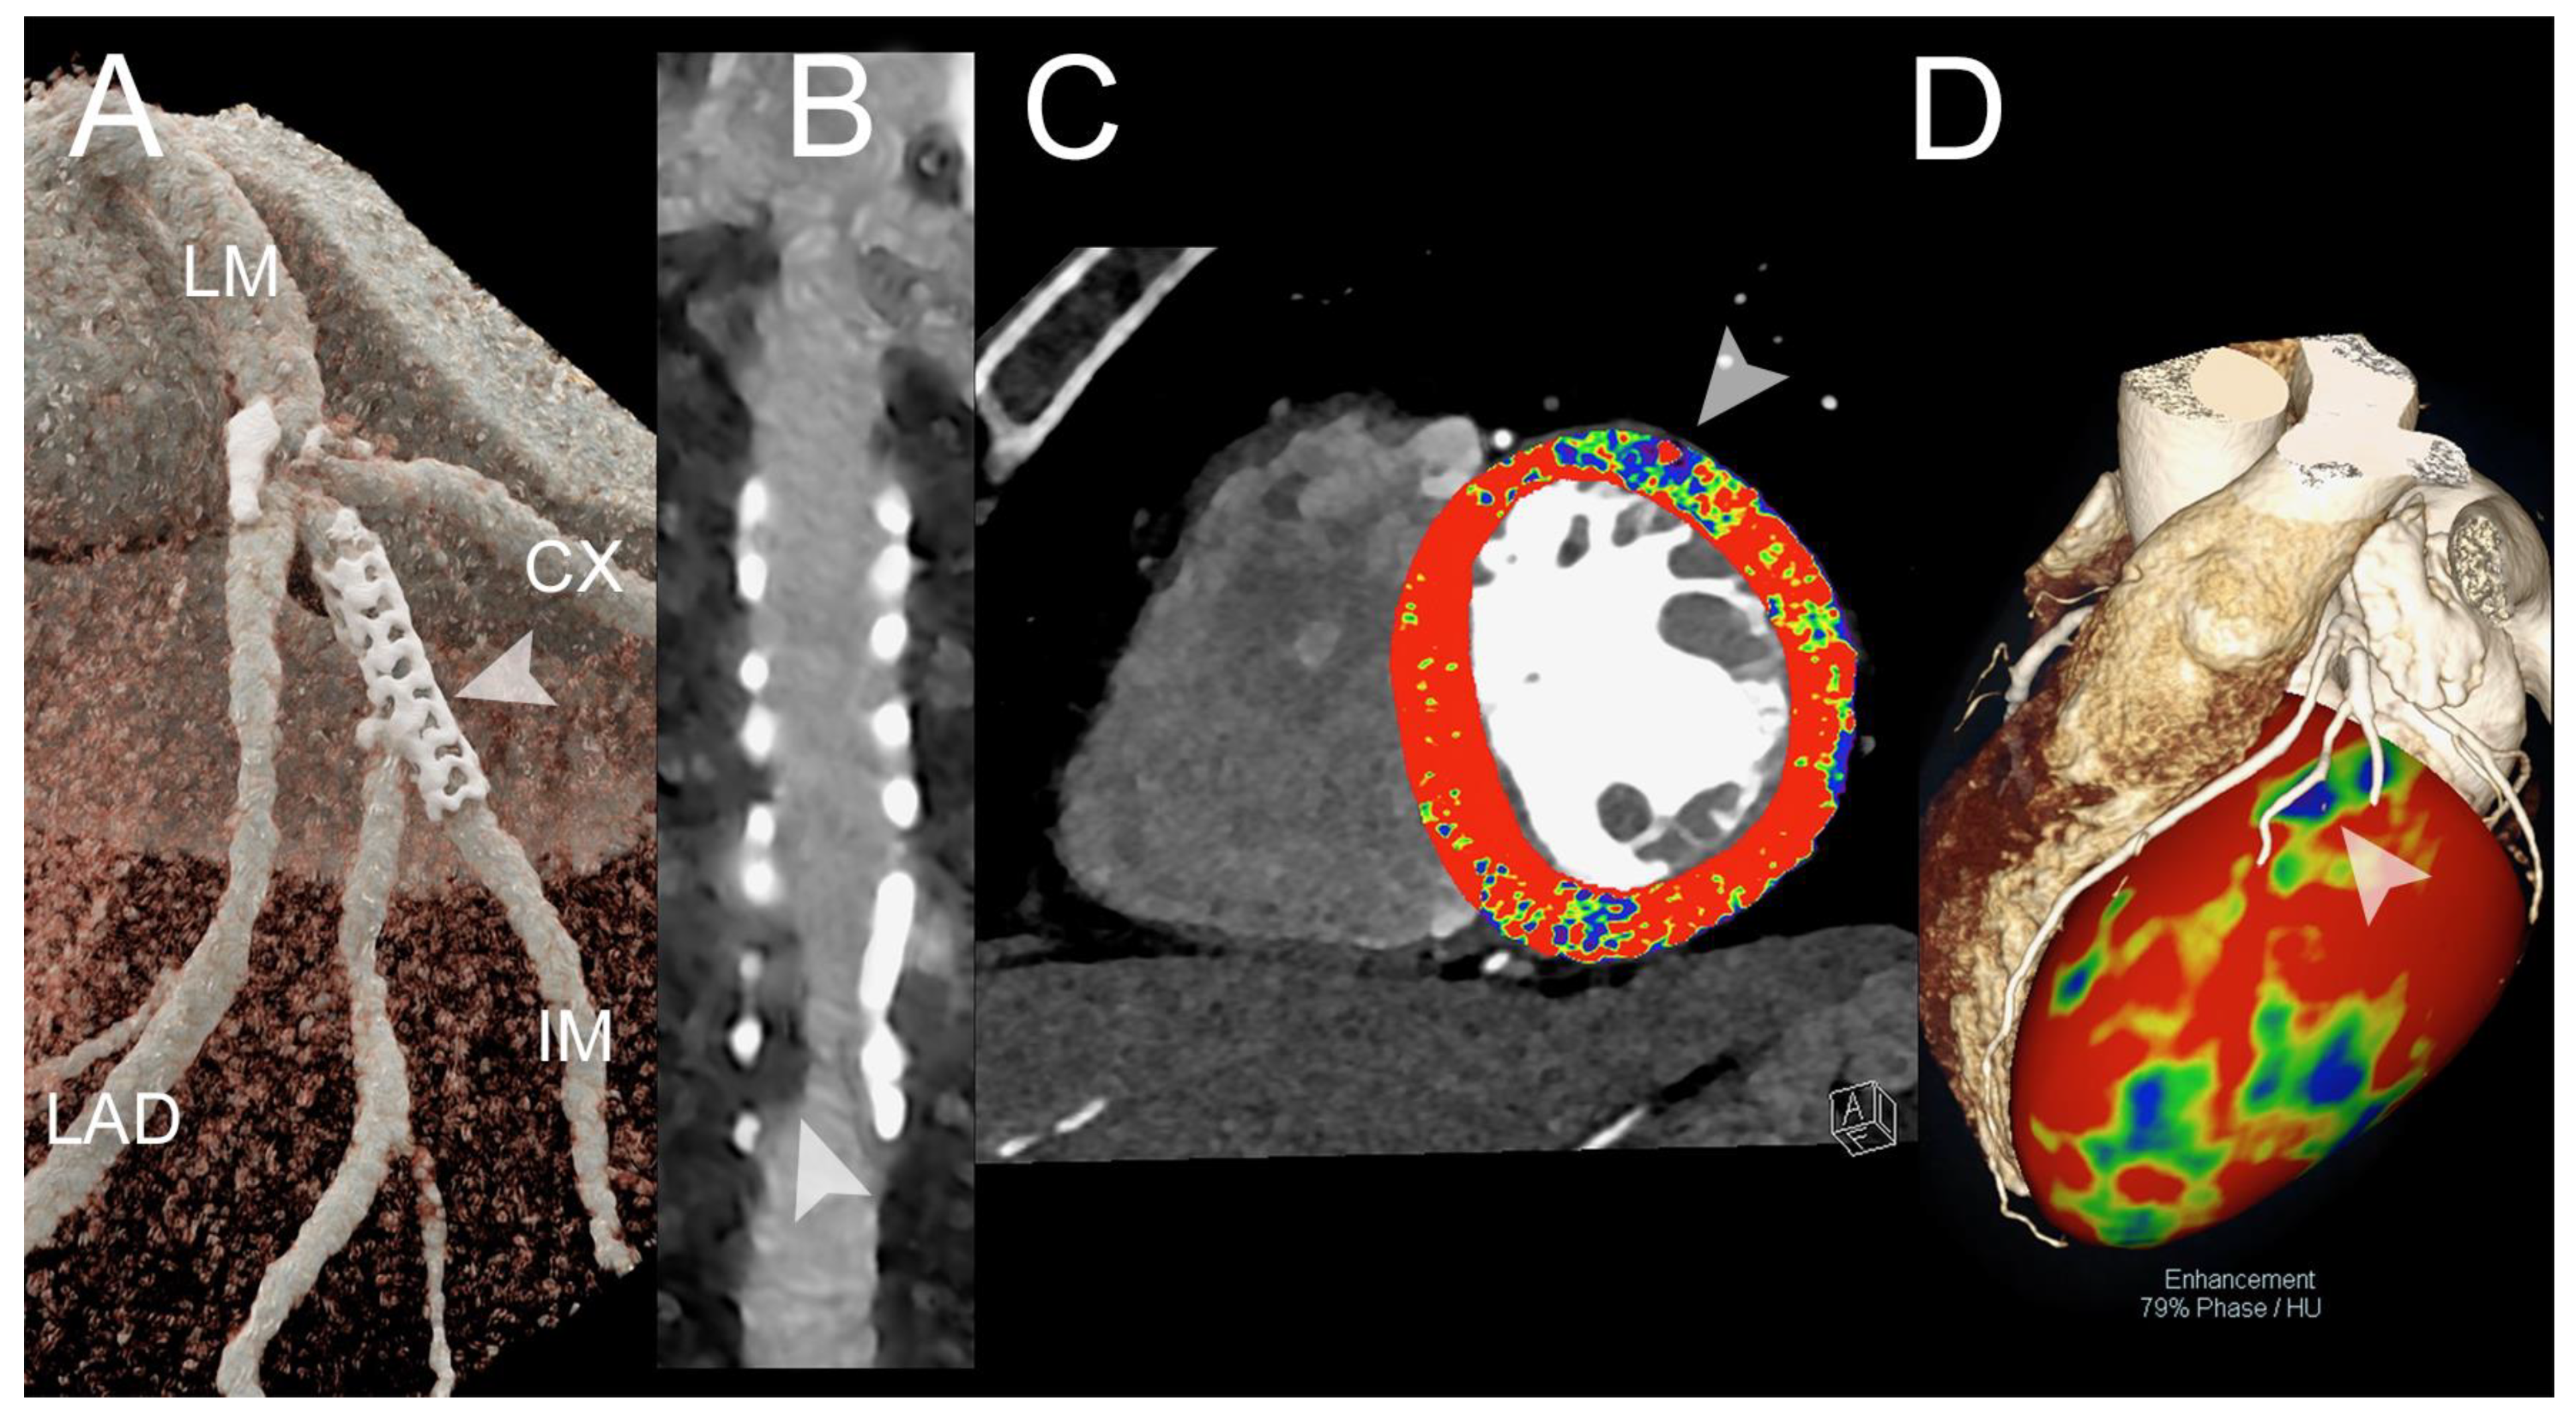

3.1. Coronary Artery Assessment

3.2. Myocardial Perfusion